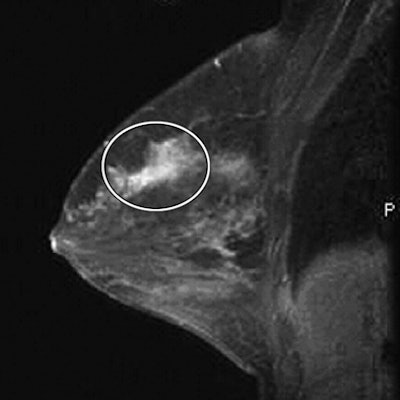

| Breast images of 46-year-old woman with biopsy-proven bilateral lobular carcinoma who presented with palpable left breast mass. MRI and breast-specific gamma imaging findings were positive. Mammogram of right breast (not shown) was negative, whereas mammogram of left breast (not shown) showed pleomorphic calcifications in upper outer quadrant. Above and below, contrast-enhanced MR images of right breast show spiculated mass (circle) at 12-o'clock position. All images courtesy of the American Roentgen Ray Society. |